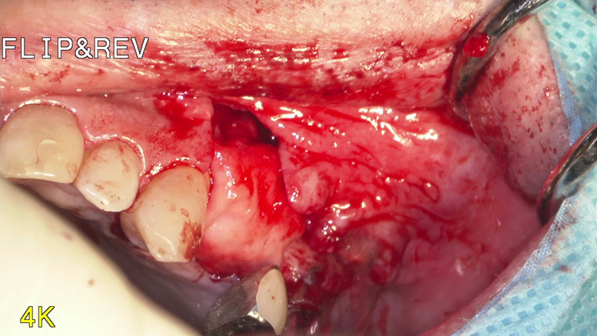

①歯根破折により右上小臼歯が動揺し、歯肉が腫れてしまい、周囲の歯槽骨が吸収していてインプラント埋入

が出来ないと他院で診断され、当院にインプラント治療を希望されました。

①歯槽頂よりサイナス

リフトを行いました。

②血液成分とカルシウム材料により骨造成をしました。